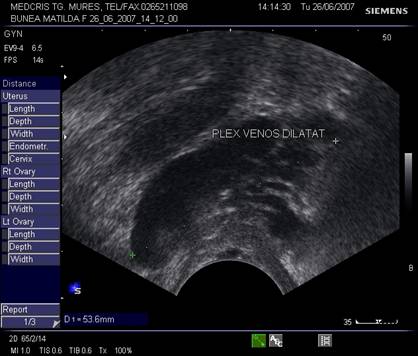

Fig. nr.395.Plex venos dilatat , parametral ( diagnostic diferential cu un chist ovarian, dificil uneori , la ecografia transvaginala )

Fig. nr.396. La ecografia tranvaginala asociata cu Doppler , plexul venos dilatat se diferentiaza facil de un chist ovarian